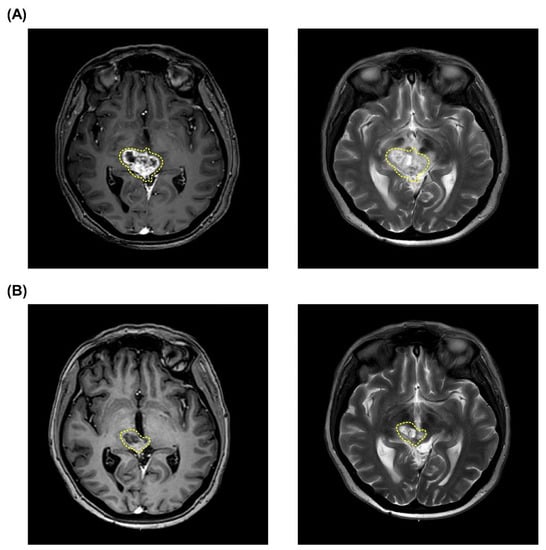

3.1.2. Case 2 (Patient #3)

| 3 | 49 | F | Pleomorfic xantoastrocitoma | Focal | 60 | 17.72 | 2.46 | 2.87 | 41.13 | 6.79 | 5.42 | 9.17 | 2.34 | 2.39 | 27.41 | 6.62 | 5.81 | 8.01 | PR | No | No |